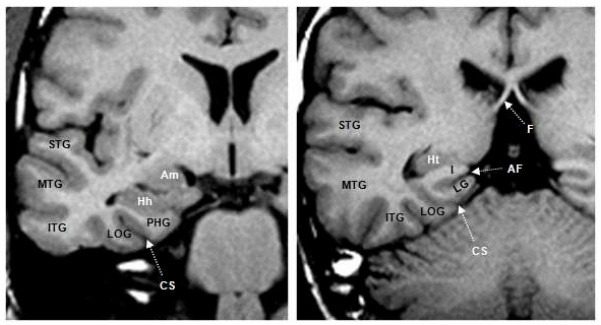

⑬ The coronal view of the brain